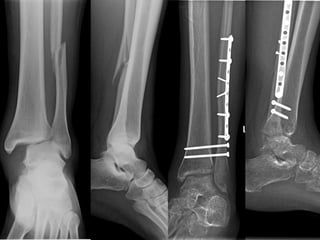

Posterior Malleolus Fracture: Fixation

Screws

Plates